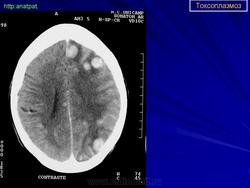

Церебральный токсоплазмоз.

Церебральный токсоплазмоз

Пато морфологи я. Патоморфологические изменения при приобретенном токсоплазмозе изучены в экспериментах на животных. Установлено, что в центральной нервной системе развиваются явления некротического перивентрикулита, мелкие очаги некроза в субкортикальном белом веществе. В сосудах головного мозга, мягкой мозговой оболочки и хориоидальных сплетениях отмечаются признаки серозно-пролиферативного воспаления. Обнаруживаются также глазные патологоанатомические изменения (типа ретинита, хориоидита, иридоциклита) и изменения во внутренних органах (сердце, легкие, печень, селезенка).

Врожденный токсоплазмоз чаще, чем приобретенный, приводит к летальному исходу. В головном мозге умерших обнаруживаются более или менее значительные очаги обызвествления, участки размягчения мозгового вещества, полости, заполненные жидкостью. Как правило, отмечается гидроцефалия, обусловленная воспалительной и рубцовой облитерацией водопровода среднего мозга, отверстий Люшка или других участков ликворных путей. Истон-чение вещества полушарий мозга может достигать степени их полного исчезновения.

Особенно характерна триада симптомов: хореоретинит, гидроцефалия, очаги обызвествления в головном мозге. Кроме того, отмечаются менингеальные знаки, тонические и клонические судороги, парезы, параличи, олигофрения.

Дифференциальная диагностика изображения